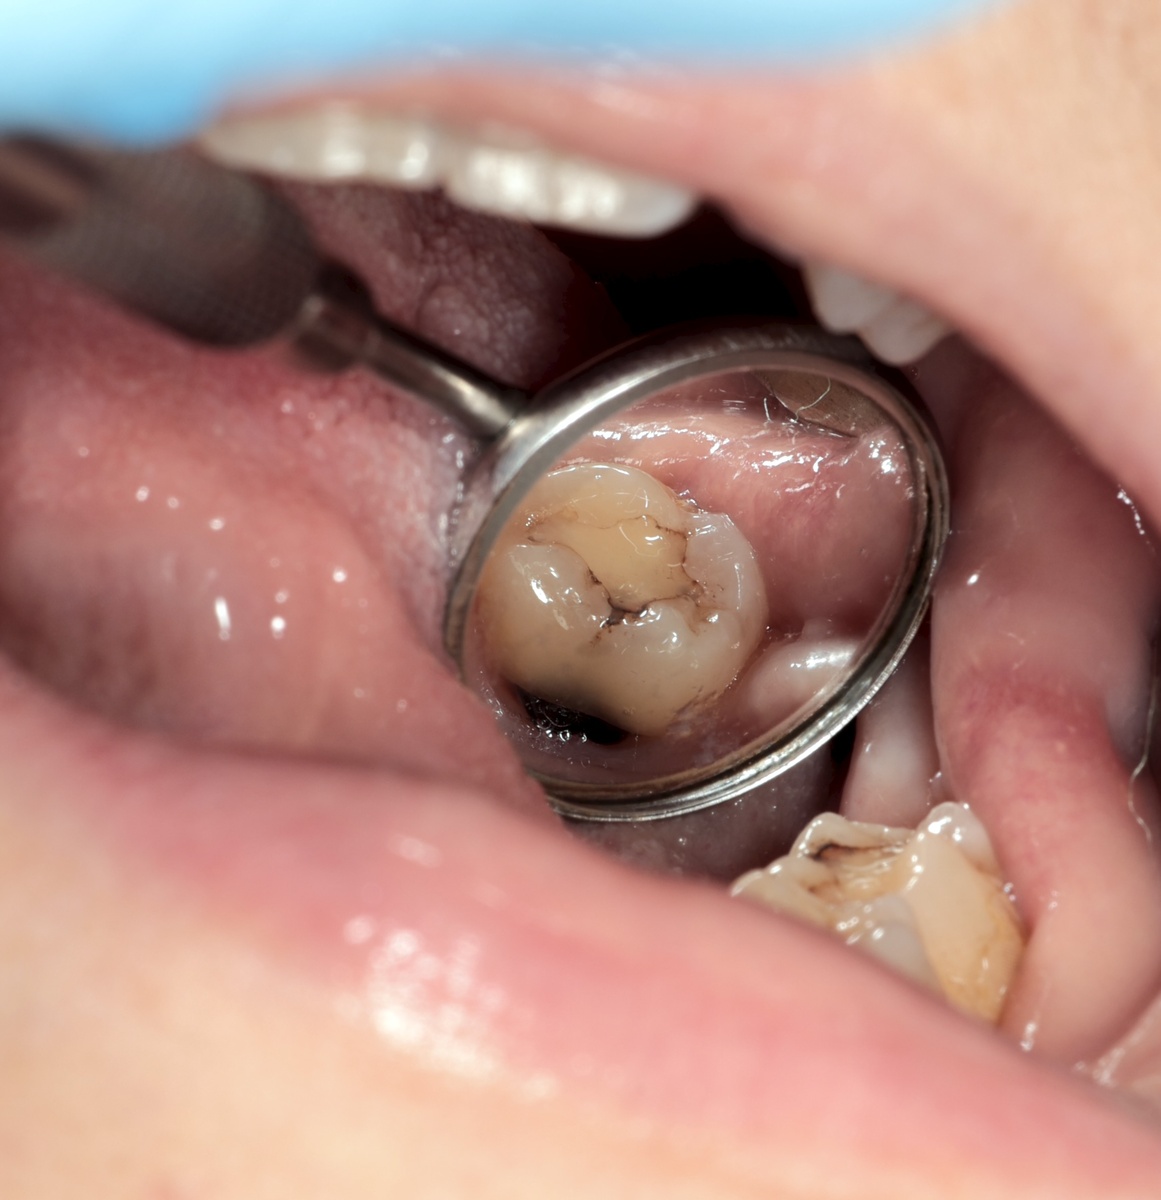

А вот и зуб 3.7, кариес в очень сложном месте - на корне с ЯЗЫЧНОЙ стороны. То есть, самая подлая локализация для "рвотнорефлексующих":

Кариес корня 3.7 зуба с язычной стороны

Очень понятно, почему за зуб никто браться не хотел. Кариес, сам по себе, очень сложный, так и ещё и рвотный рефлекс в нагрузку. И, пожалуй, именно второй фактор вызывал отказы.

Серьёзный такой кариес